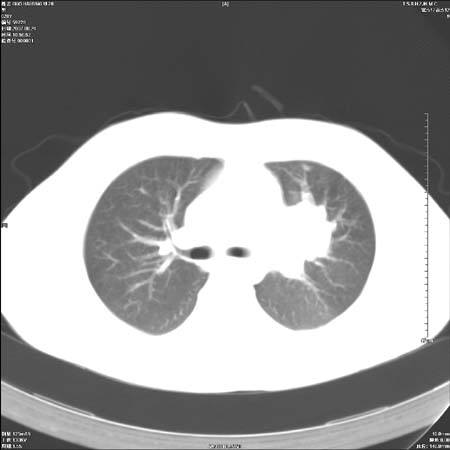

首先这个病例应该加薄层面扫描-可以很好显示支气管与肿块的情况。

鉴别:中央型肺癌-肿块那么明显一般合并节段肺不张或阻塞性炎症。

本例肿块边缘外侧可见左上叶各段支气管。

肺癌可能性大。(有分叶,毛刺)

左侧肺门区见一块状病灶可见分叶,纵隔内及左肺门见肿大淋巴结,应该是周围型肺癌而不是中心型肺癌,原因有以下2点,1未见阻塞肺气肿和阻塞性炎症,这么大肿块如果是中心型肺癌就是未分化型或小细胞型肺癌不出现阻塞性肺不张也应该有阻塞炎症或阻塞性肺气肿,2如果是中心型肺癌临床出现最早的症状是咳嗽(此时可无任何异常影象),而此人这么大肿块只有背部隐痛是体检才发现无法解释.

左肺门区分叶状软组织肿块,纵隔内有肿大淋巴结,诊断肺癌应该问题不大。

直接下肺癌诊断还太早,病灶较大,估计5cm以上,但阻塞性改变及对临近纵隔及支气管侵犯不明显,密度较均匀,弓旁见一单个淋巴结,需要排除炎症性肿块及腺瘤,平滑肌瘤等。